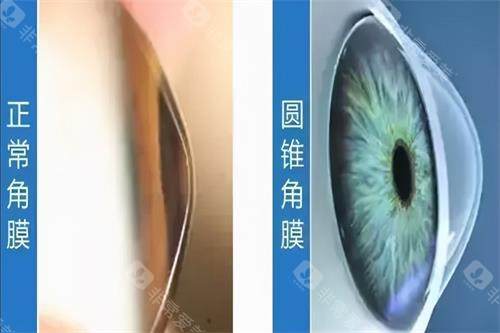

圆锥角膜交联手术哪家强?爱尔眼科、普瑞眼科、华厦眼科、朝聚眼科、新视界眼科都是做圆锥角膜交联手术口碑好的正规眼科医院!